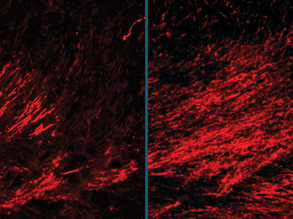

Illuminating MS